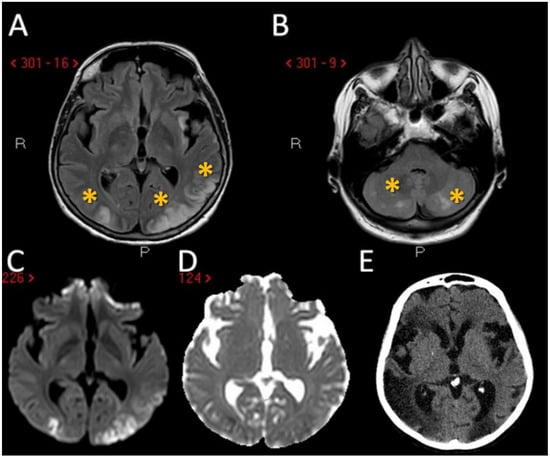

The second patient is a 64-year-old woman with a previous history of arterial hypertension and paroxysmal atrial fibrillation, on antiplatelet treatment with aspirin and rhythm control with flecainide; she also reported asthma and recurrent sinusitis (a prior sinus CT had displayed severe inflammation of the paranasal sinuses). She arrived at our attention because of bilateral upper limbs paraesthesia followed, the next day, by psychomotor slowing, right upper limb weakness, instability, and difficulty with walking. Neuroimaging exams (head CT and MRI) revealed multiple bilateral cortical-subcortical ischemic lesions in the cerebral and cerebellar hemispheres, mostly located in border zone areas (Figure 2A–D); no stenosis or occlusion in the head and neck vessels was detected on CTA and MRA.

Figure 2. Brain MRI of the second patient. MRI of patient 2 showed the presence of multiple scattered hyperintense brain lesions on both internal border zone (green asterisk) and on cortical location (red asterisk) at axial FLAIR sequences (A) with diffusion weighted imaging (DWI) and apparent diffusion coefficient (ADC) pattern suggesting acute ischemic lesions with a metachronous timing pattern (B,C). In the follow-up MRI performed 3 months later it is evident the chronical evolution of the above-mentioned ischemic lesions (D).